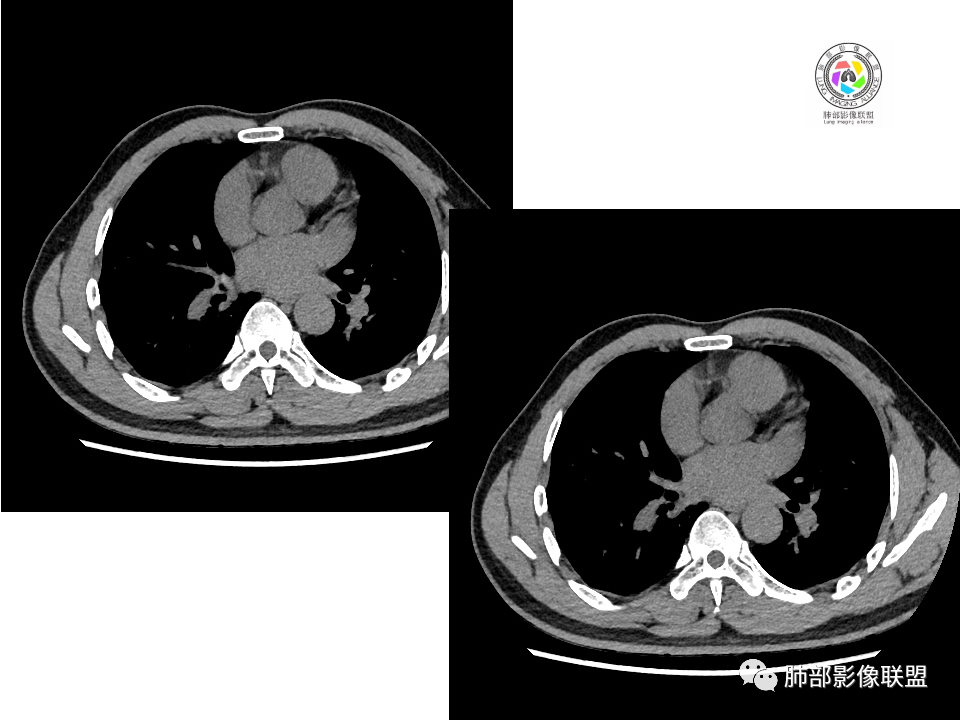

2.右肺下叶背段胸膜下块影,边界清楚光整,上下极见磨玻璃晕,未见明显分叶毛刺和棘状突起,未见胸膜凹陷或胸壁侵入。密度均匀,轻度不均匀强化。未见支气管进入。

3.右肺中叶外侧段胸膜下散在小片影,磨玻璃密度为主,边界不清,支气管相关。符合炎性特征!

2.边缘光整,会是小细胞癌或是大细胞癌吗?小细胞癌的肺门纵隔淋巴结增大往往十分夸张,该患者不符合。

5.慢性感染灶。缺乏临床表现,强化不显著会想到继发性肺结核,背段病灶过于光整均匀,周边过于干净使人狐疑,且“成掎角之势”的中叶病灶结核灶特点也着实不多。

有老师分析,多发病灶有磨玻璃晕,可以符合隐球菌感染,确实如此。但背段边缘如此锐利的块影还是更容易让人联想到新生物。